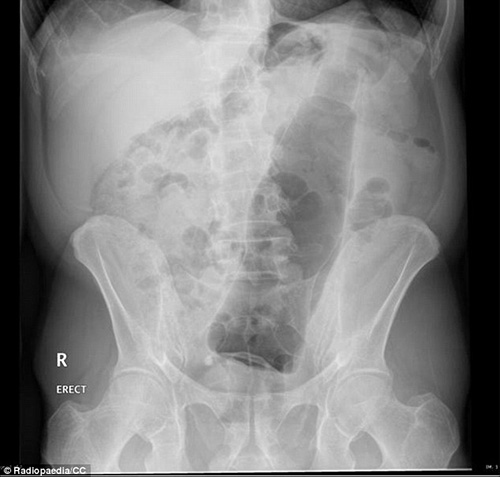

VBF- Đây là các hình ảnh được cung câp bởi các bã sĩ trong bệnh viện. Các bênh nhân sau khi để lọt các đồ vật vào người đã phải đi cấp cứu tại bệnh viện và đã được chụp X-quang để xác định đồ vật đó.Đó thường là những "vật dụng bất bình thường" được các bác sĩ khắp thế giới tìm thấy bên trong trực tràng của các bệnh nhân và chia sẻ trên trang Radiopaedia, một website giáo dục và thảo luận do các sinh viên X-quang thành lập từ năm 2005. Hình ảnh X-quang được chia sẻ trên website là vật mẫu cho việc nghiên cứu hợp tác và là giáo cụ trực quan trong giảng dạy ngành học quang quyến (môn học X-quang), hoặc dùng làm tài liệu cho các bảo tàng, đồng thời là những ví dụ giúp mọi người cảnh giác. hiếc chày trong trực tràng người đàn ông 40 tuổi được "khổ chủ" giải thích khi nấu món ăn Malaysia đã bị trượt vào trong??? Một chai đựng cà phê với những chiếc ghim gắm vào lớp cao su phía dưới nắp được bệnh nhân đưa vào trong cơ thể. Một tuýp đựng vitamin được đưa vào trong trực tràng. Thậm chí một chiếc chai cũng nằm trong danh sách bộ sưu tập các bác sĩ X-quang thu thập được. Dụng cụ rung được đưa vào qua đường hậu môn. tm tm